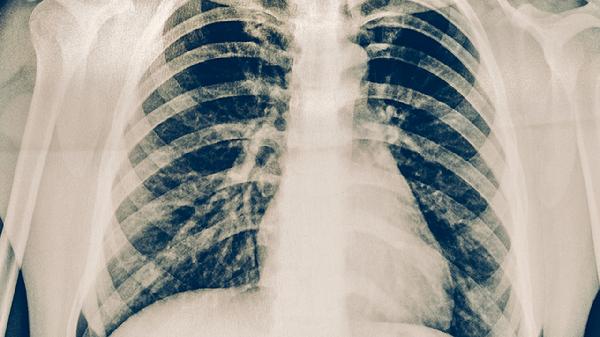

肺结核通过中医治疗可以缓解症状,但无法完全替代西医抗结核治疗。肺结核的治疗需以西医抗结核药物为主,中医可作为辅助手段改善体质、减轻药物副作用。主要有中西医结合治疗、中药调理、针灸辅助、饮食调养、情志调节等方式。

规范的四联抗结核药物(异烟肼片、利福平胶囊、吡嗪酰胺片、乙胺丁醇片)是根治肺结核的核心方案。中医可在医生指导下配合使用百部止咳糖浆、百合固金口服液等中成药,帮助缓解咳嗽、盗汗等症状。治疗期间需定期复查胸部CT和痰培养。

肺结核患者需严格完成6-8个月的抗结核疗程,中医治疗期间不可自行停用西药。注意保持居室通风,佩戴口罩防止飞沫传播,餐具应煮沸消毒。每月复查肝功能,出现视力模糊、皮肤黄染等药物不良反应时及时就医。恢复期可适当进行太极拳等温和运动增强肺功能。